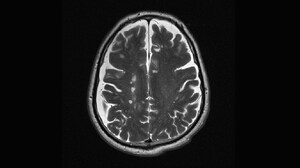

Multiple Sclerosis: Making the Diagnosis With ...Diagnosis of multiple sclerosis may take months to years because this condition is defined either by recurrent or by gradual and progressive episodes of symptomatic central nervous system demyelination.